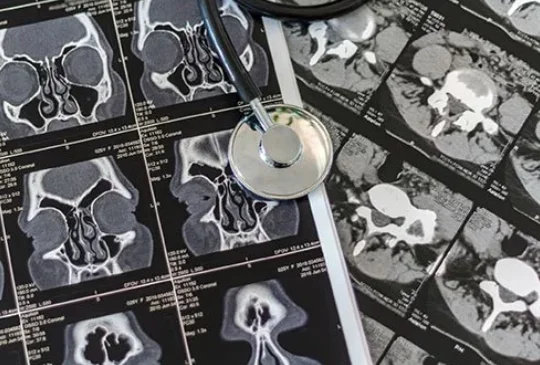

جراحی آندوسکوپی سینوس: آیا درمان قطعی سینوزیت با جراحی امکانپذیره؟

اطلاعات این مقاله برای کمک به افرادی است که در حال آماده سازی خود برای جراحی آندوسکوپی سینوس هستند و اطلاعاتی در مورد این جراحی ندارند.